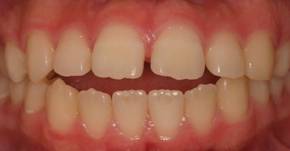

インビザGOによる矯正症例1 16歳男性

マウスピース矯正開始前。右上犬歯が内側にありました

前から見たところ